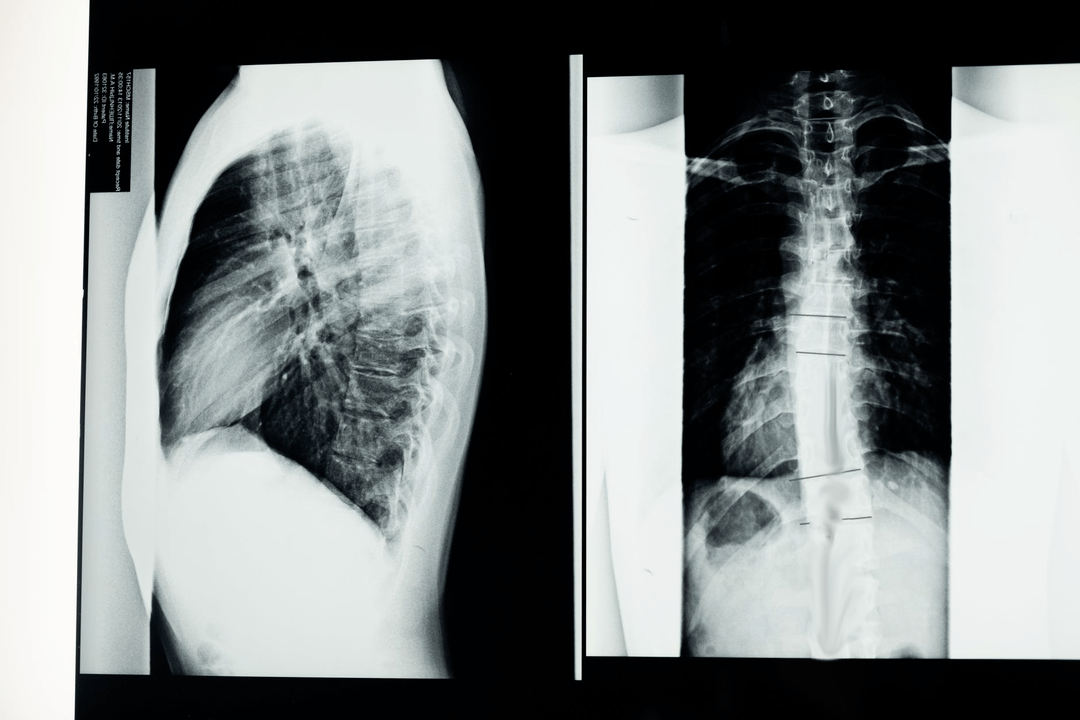

Before starting diagnostic studies, the neurologist collects the patient's medical history and carefully studies his complaints.Osteochondrosis has symptoms common to some other diseases, so it is important to know how to differentiate the pathologies.X-ray studies will help confirm the diagnosis of osteochondrosis: radiography, myelography and computed tomography.

A survey x-ray allows you to obtain an x-ray image of the spine or a section of it.This way, the doctor will be able to determine the location affected by the disease.For greater clarity, we will explain how osteochondrosis can be determined by radiography: the image will show a narrowing of the intervertebral disc, the presence of bone growths (osteophytes) or a change in the shape of the spinal segment.